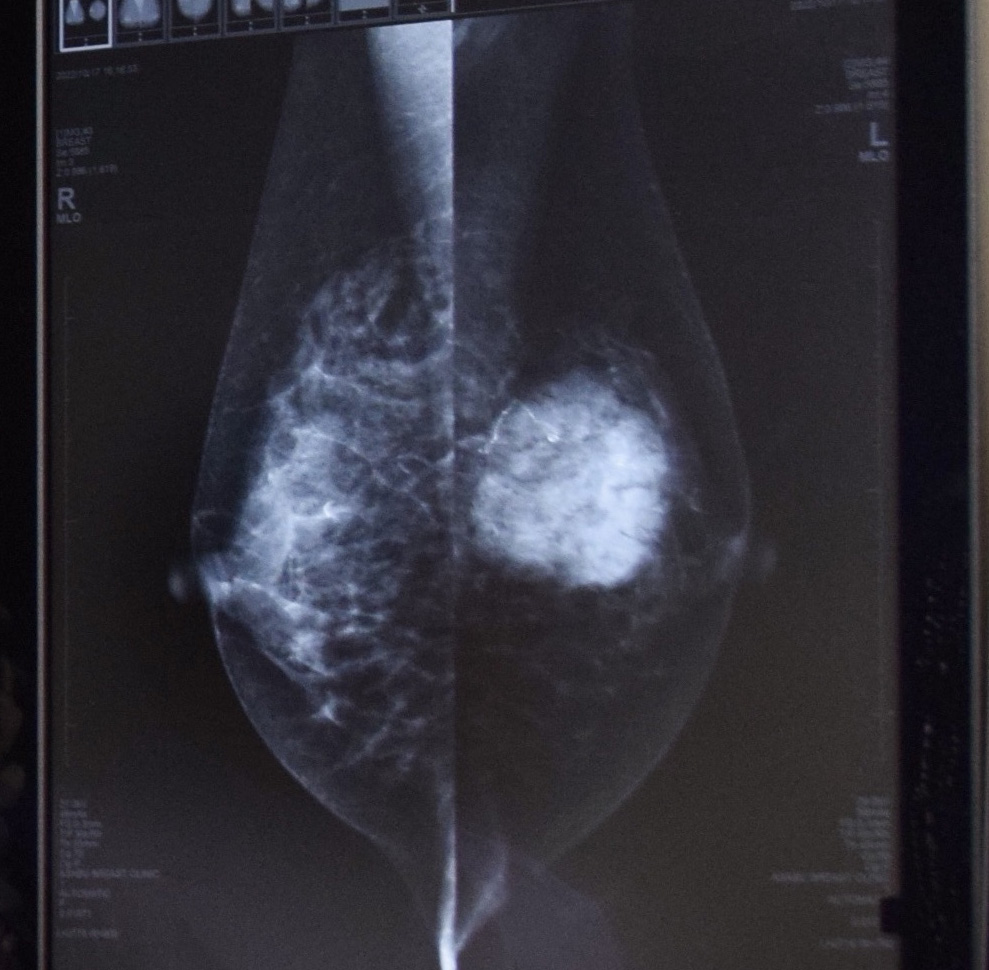

右側の丸く白い部分が乳がん組織

(マンモグラフィーの診断画像)